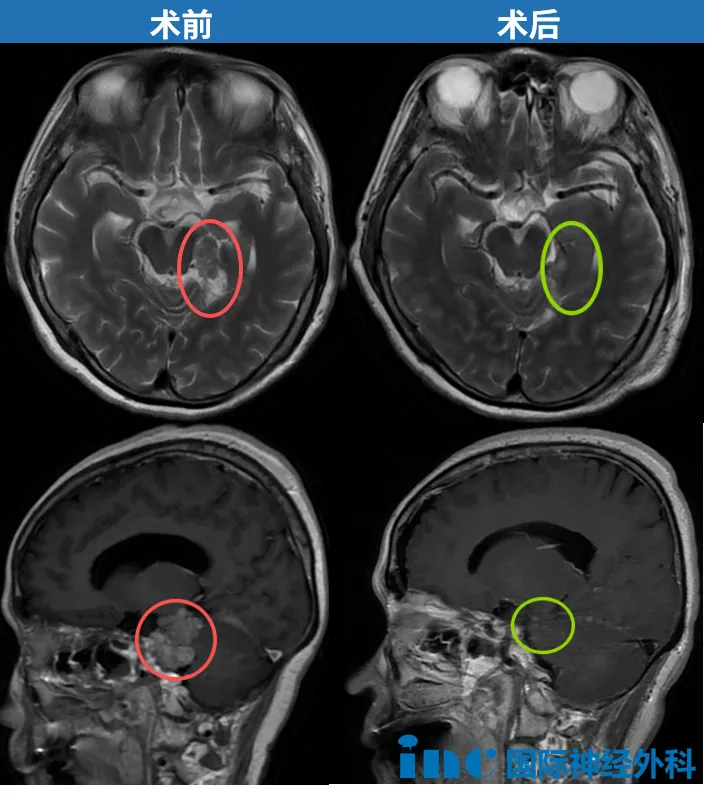

病灶现已完全消失。影像学检查显示无肿瘤残留或复发迹象,所...